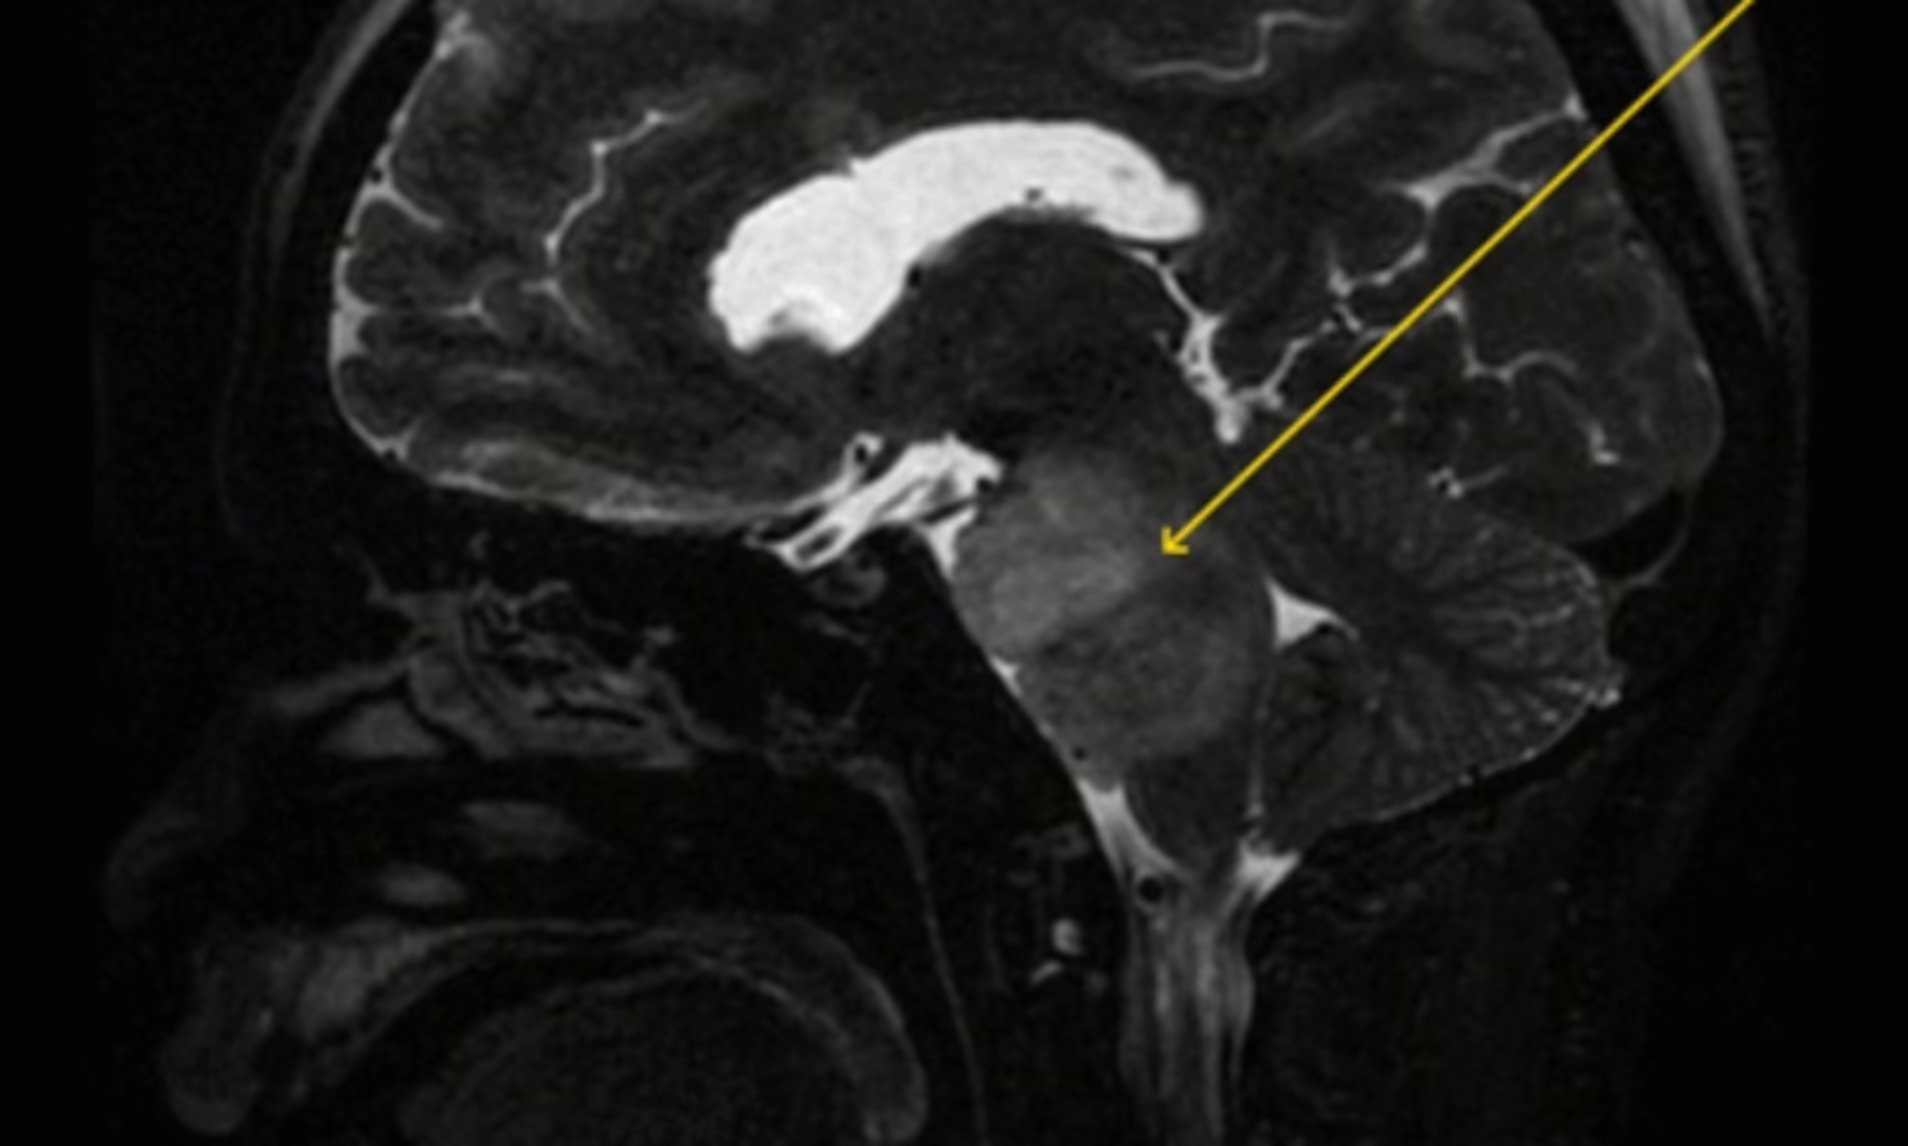

Keputusan pengimejan resonans magnetik (MRI) yang dilakukan menunjukkan lelaki itu menghidap penyakit glioma pontine intrinsik iaitu sejenis tumor otak yang sangat agresif dan sukar dirawat.

Pontine glioma adalah kanser yang mustahil untuk dibuang melalui prosedur pembedahan kerana komplikasi dan risikonya terlalu tinggi.